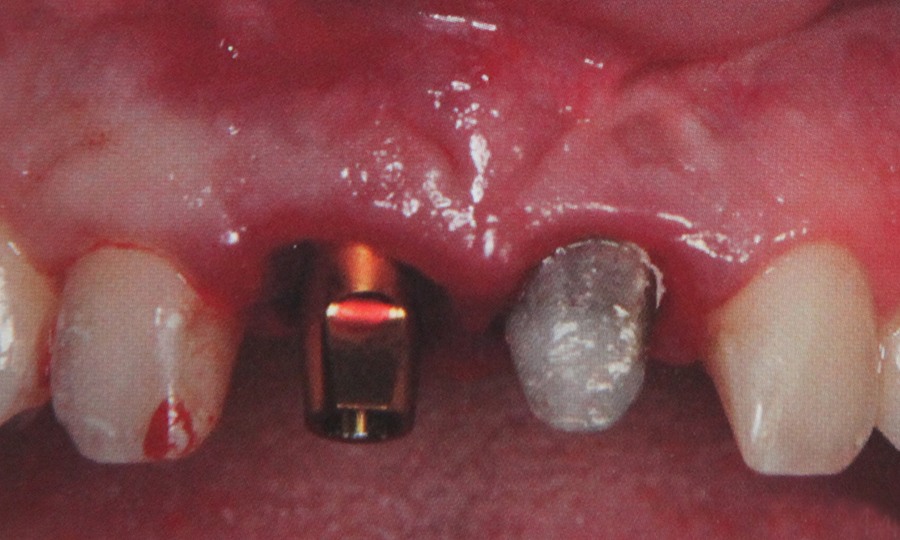

Implantele dentare reprezinta la ora actuala singura posibilitate de a inlocui dintii lipsa prin protezare fixa rezultand o dentitie foarte apropiata de dintii naturali. Implantele dentare sunt niste radacini artificiale realizate din titan care se insera in os. Dupa o perioada de aproximativ 6 luni perioada necesara pentru integrarea implantului, acestuia i se ataseaza un bont protetic pe care ulterior se fixeaza coronita de ceramica sau proteza.

Implantele sunt recomandate pentru pacientii de toate varstele carora le lipsesc dintii. Oricine este suficient de sanatos pentru o mica interventie chirurgicala in cavitatea bucala poate apela la tratament prin implant.